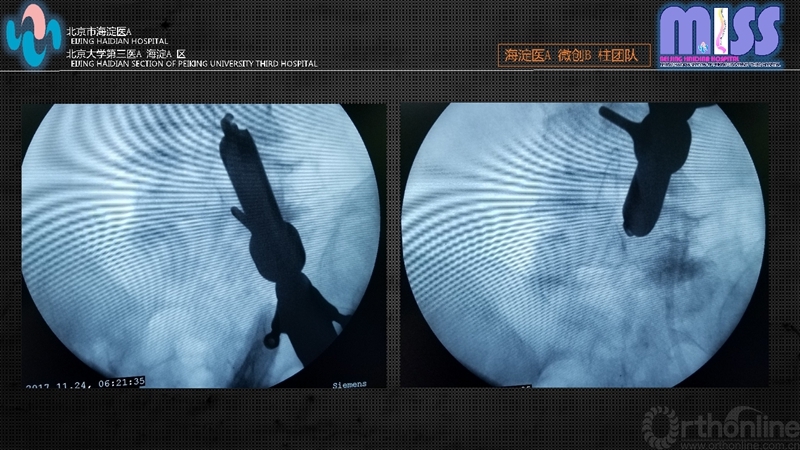

透视定位手术节段,单侧症状者由症状侧标记责任节段关节突关节内侧缘,双侧症状者全部选用右侧。透视监视下18G穿刺针穿刺至关节突关节内侧缘并适度滑下至黄韧带表面,替换为导丝后切开1cm皮肤、皮下及深筋膜,逐级软组织扩张导管扩张后拧入工作套管,斜面朝向黄韧带,透视证实位置。